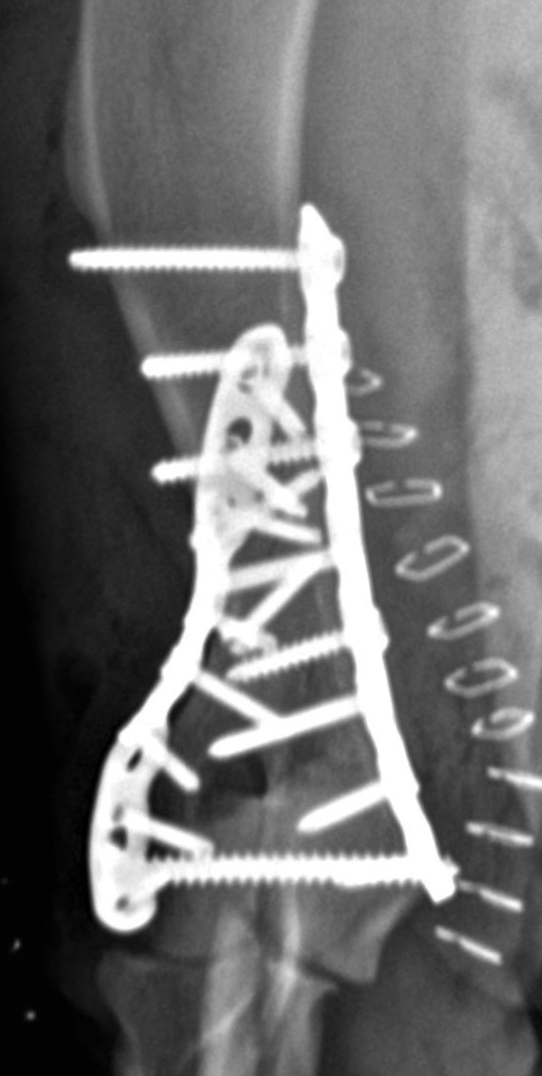

Prompt and accurate repair is critical. Surgery typically involves placement of a transcondylar screw to stabilize the fracture, often paired with plates or pins for additional support. Bicondylar fractures are especially challenging because the elbow is effectively split into three pieces, requiring meticulous reconstruction.

Humeral condylar fractures require surgeons with extensive experience and specialized tools. At AOCF, advanced imaging (CT and fluoroscopy) helps us understand the fracture before and during surgery. We maintain a full range of implants for even the most complex repairs and use minimally invasive techniques when appropriate. This approach ensures precise reconstruction, faster recovery, and the best possible long-term outcome for your pet.